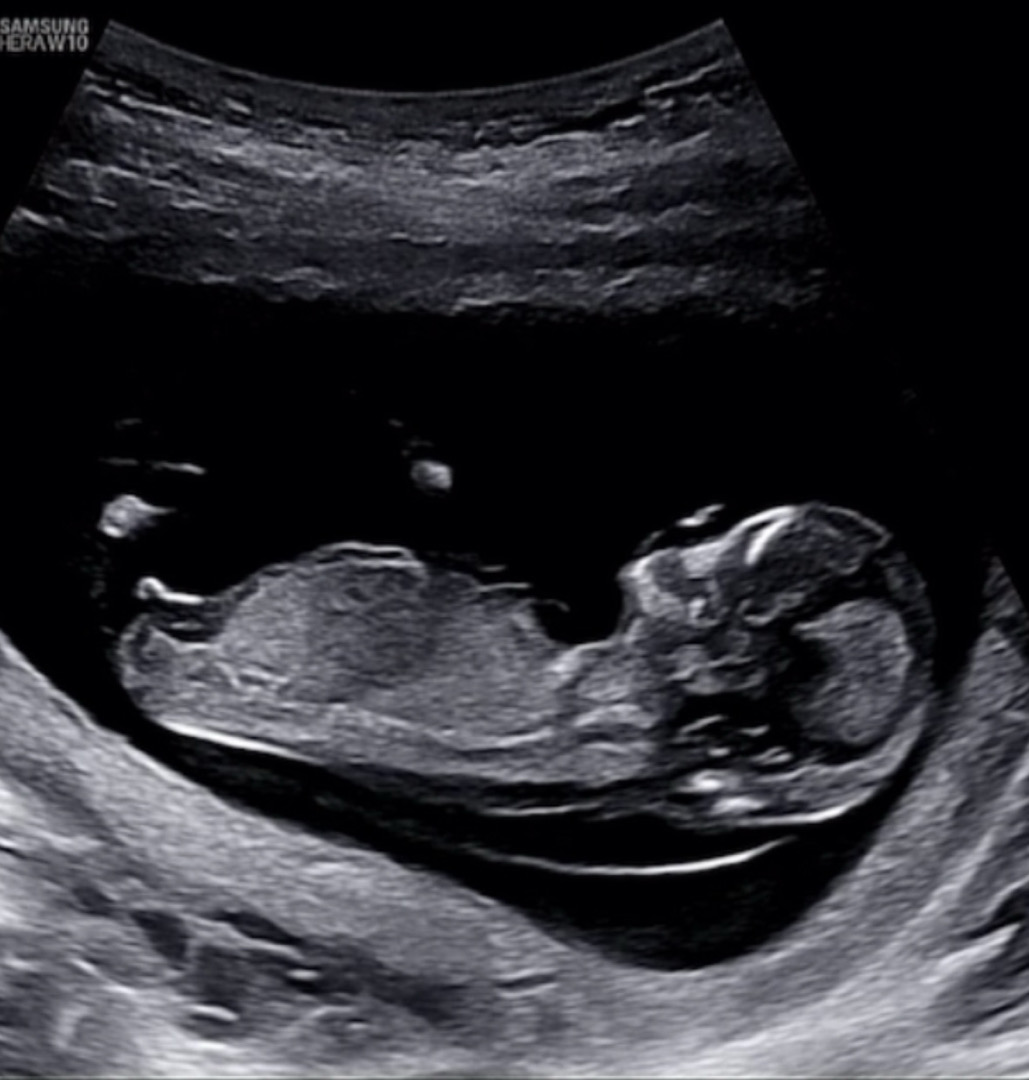

12주4일 각도법 한번 봐주세요!

아들일까요 딸일까요~?

아들같아요~!

아들같아요!